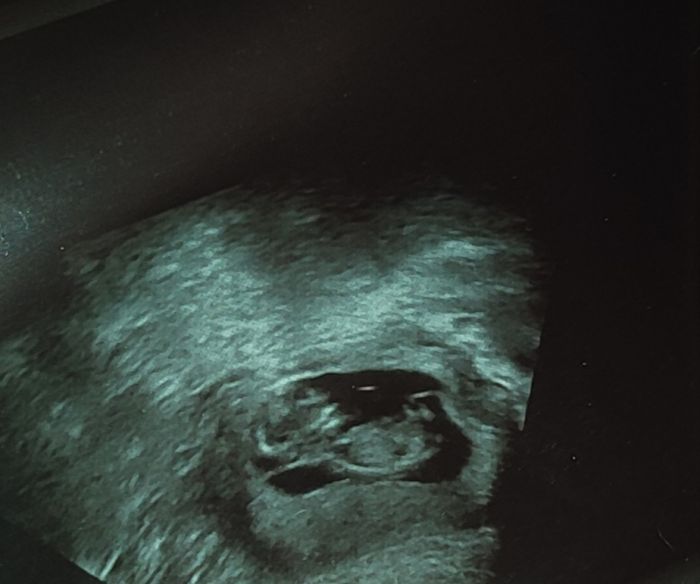

Ahoj, vyzná se tady někdo v určení pohlaví .? Dnes jsem 12+1.tt.